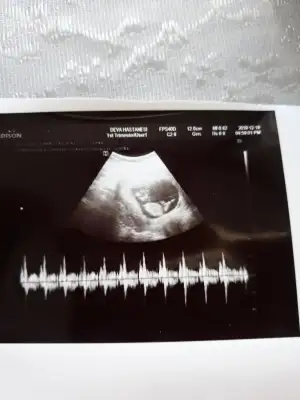

Benim buna göre, Çin takvimine, Rus takvimine, kesedeki konum ve nuba, doktorun ilk tahminine, hepsine göre tuttu bu sefer😀 Tam hepsine inanacak oluyorum, oğlumda hiçbirinin tutmadığını hatırlıyorum😬 nub ve kese konumunu bilmiyordum o zaman ama, takvimler ve 12. hafta doktor tahmini tutmamıştı.